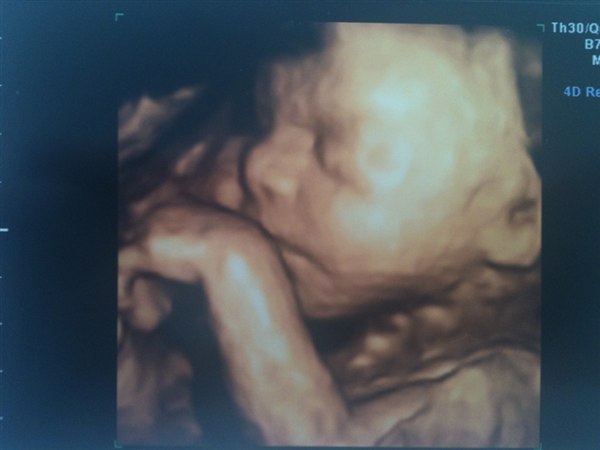

Billede 1+2 er truntens ansigt